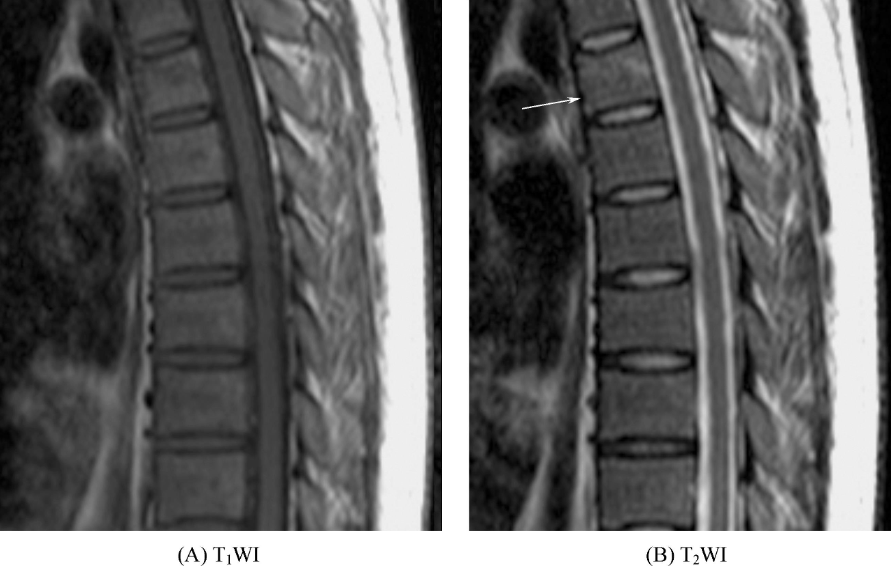

③椎体骨挫伤。椎体形态不变,椎体内可见长T1、长T2信号(图4)。

图4 椎体骨挫伤胸5椎体内见斑片状长T1长T2信号影,椎体形态未见异常。